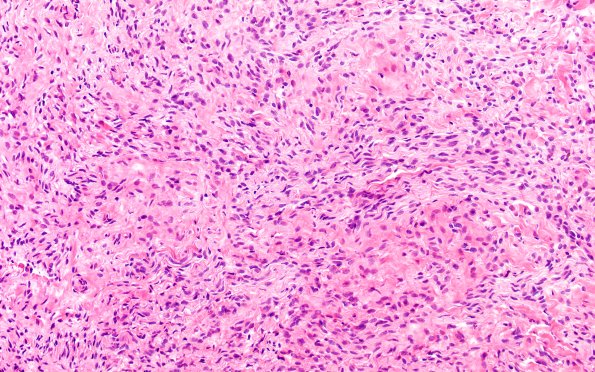

Washington University Experience | PERIPHERAL NEUROPATHY | 19 TRAUMATIC INJURIES | 14A3 Neuroma, traumatic (Case 14) H&E near DRG 20X 2

Higher magnification of the mini-fascicle (14A2) and haphazard collections of regenerating axons (14A3). (H&E)